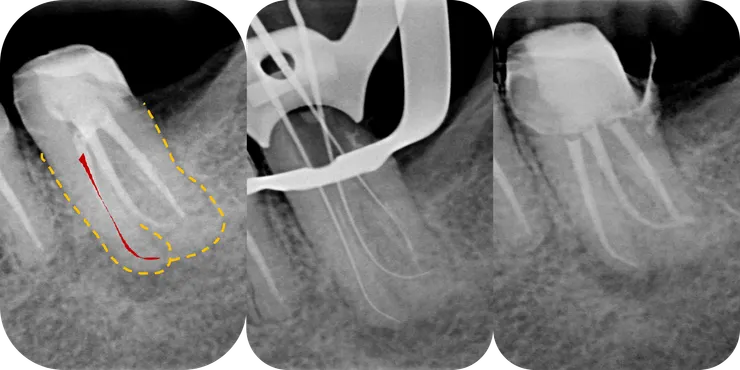

如同開場白強調的,任何 case 在開始前,務必、千萬、一定要先看清楚 root form (橘色虛線) & canal path (紅線)!

就算 canal 鈣化到看不到,也可以依據 root form 來推測出 canal 可能的走向。

如右圖所示,從依據 root form 推測出的 canal path 看來,原本的路徑似乎偏移不大,是不是繼續往下鑽就可以了呢?

果然,從 CBCT 才能看清真相!

(因為 B & D canal 的關鍵點太深了拍不到,因此本篇只 focus 在 ML canal.)

不光是 PA film, 在 CBCT 上我們也可以依據 root form 推測出 canal 的走向 (如下排圖中的紅色標示處)。於是我們可以清楚地看出,先前的路徑 (粉紅色箭頭標示處) 明顯地往 lingual & mesial 偏移,並勘勘在 perforation 前停住......

如圖所示,這次我們把重點擺在 DB canal.

先畫出 root form & canal path.

可以發現,前一位醫師的路徑有些許偏移,然後在 canal 中段彎折處 (紅色箭頭所指處) 製造出 ledge 而因此卡住......

一番掙扎後決定拍張 X 光片看看 ---

結果發現到達的深度跟前一位醫師一模模一樣樣...... (比較圖 1 & 4)

然而不同的是,經過 coronal enlarge 後,此時 file 的自由度變大了 (注意到紅色箭頭所指的 orifice 附近的彎度變直了),file tip 的手感就變清晰了!

再搭配圖 2 得知路徑應往 mesial 修正,搭配圖 3 得知 canal 中段以下往 buccal 彎,於是我在 file tip 1mm 處彎了一個小小彎,往 M/B 方向找 --->

就找到了原本的 pathway 完成了這個 case.